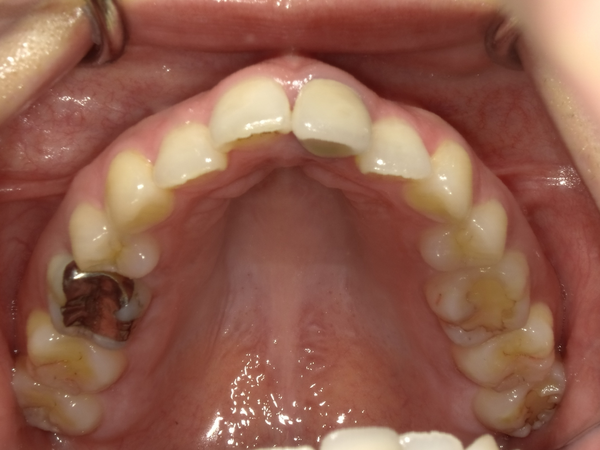

befor→after

●ご相談内容:歯の出っ張り●矯正の種類:マウスピース型矯正「インビザラインGO」●治療期間:13週間●治療費用:44万円(税込)